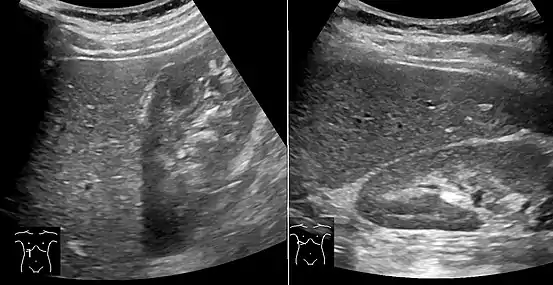

On abdominal ultrasonography, steatosis is seen as a hyperechoic liver as compared to the normal kidney.

Abdominal ultrasonography with the liver and kidney side by side (left image) may give a false impression of hyperechogenic liver, so it's preferably done with the organ borders facing the ultrasound probe (right image, of the same case).

Abdominal ultrasonography of focal steatosis. It is distinguished from a tumor by not compressing the hepatic vein.